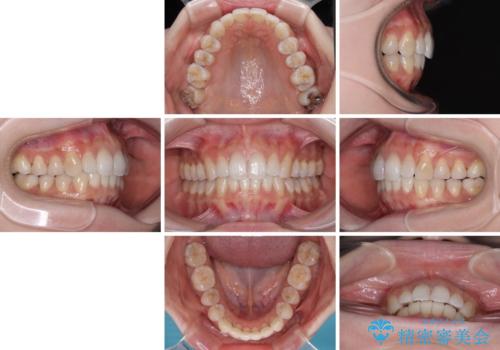

歯列としてはインビザラインでもワイヤー矯正でも対応できるものでしたが、奥歯の咬み合わせを見た時に上顎がやや前方にあり、インビザライン単独では時間のかかってしまう可能性があるため、補助装置を治療当初に使用することで、インビザラインによる治療をスムーズに行えるように計画しました。

インビザラインは得意・不得意の差がはっきりとしているため、補助装置やワイヤー装置などをうまく活用することで、治療期間を短縮するとともに、より理想的な仕上がりを達成することができます。